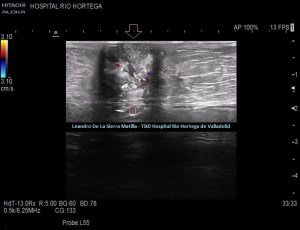

Durante el estudio del peritoneo, retroperitoneo y cadenas linfáticas abdominales, observamos una lesión superficial, redondeada, heterogénea, hipo-Isoecogénica con zonas hiperecogenicas, de aspecto sólido.(FIGURA 4)

4

Cambiamos a una sonda lineal para un estudio más detallado, observando una LOE hipoecogénica con zonas híper-isoecogénicas, heterogénea, sólida, sin contenido de asas intestinales ni de grasa, con bordes mal definidos y con flujo doppler en su interior, ubicada dentro de la cavidad umbilical (FIGURAS 5, 6 Y 7)

5